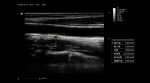

Medición automática del espesor íntima-media. IMT.

Con IMT, se puede detectar y medir automáticamente el espesor de la íntima-media y se puede generar un informe de espesor de la íntima-media, lo que proporciona predictores independientes para la prevención de eventos cardiovasculares.

Imágenes clínicas extraordinarias